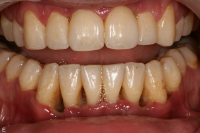

Parodontal stabilitet karakteriseras av framgångsrik behandling genom kontroll av lokala och systemiska riskfaktorer, vilket resulterat i

• minimal blödning vid sondering (BVS < 10 % av tandytorna)

• fickdjup < 3 mm

• ingen progressiv parodontal nedbrytning/vävnadsförlust

• optimal förbättring i övriga kliniska parametrar hos behandlad parodontitpatient.